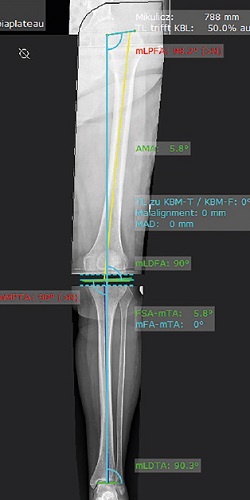

Việc thay thế khớp gối có thể được lên kế hoạch theo hai mặt phẳng (Trước sau và Trong ngoài) bằng cách sử dụng mô-đun “Knee”. Các chỉ số lệch trục của chi dưới có thể được xác định và sửa chữa trong quá trình lập kế hoạch.

mediCAD® thực hiện việc sửa chữa lệch trục này một cách tự động hoặc bằng thông số tùy chỉnh, tùy thuộc vào mục tiêu mong muốn. Phần mềm sẽ tính toán trục cơ học mong muốn, toàn trục chi dưới và tất cả các góc có liên quan sau mổ.

Việc lập kế hoạch được thực hiện đồng thời dựa trên hình ảnh X quang của toàn bộ chi dưới ở mặt phẳng thẳng và một phần của mặt phẳng bên. Cách tiếp cận này cho phép tối ưu hóa đánh giá đối với lồi cầu sau xương đùi.

Tất cả các chiều của diện cắt đều được xác định và mọi sai lệch gióng trục đều được xác định và sửa chữa một cách tự động sau khi các điểm mốc giải phẫu có liên quan được tự động nhận dạng bằng chức năng “Autoplan Knee”